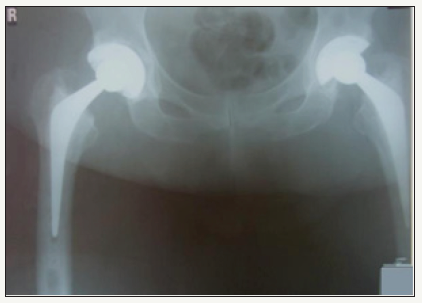

A 64 year old male underwent right total hip arthroplasty for osteoarthritis (Figure 1). A 58mm Pinnacle sector 2 acetabular cup with a neutral Marathon polyethylene liner (28mm ID x 58mm OD) was mated via a 28mm+5 high offset stainless steel Articul/Eze femoral head (12/14 cone) to an uncemented No 14 Corail stem. Post-op recovery was uneventful. Post-op X-Rays showed 37° of inclination of the cup (Figure 2).

figure 1: AP Pelvis showing right hip osteoarthritis.

figure 2: Post-op right total hip arthroplasty.